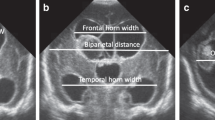

This is a retrospective study of newborns (gestational age <29 weeks) diagnosed with IVH. Clinical variables known to increase the risk for post-hemorrhagic hydrocephalus were collected. The first CUS with IVH was identified and a slice in the coronal plane was selected. The frontal horns of the lateral ventricles were manually segmented. Automated quantitative morphological features were extracted from both lateral ventricles. Predictive models of the need of temporizing intervention were compared.